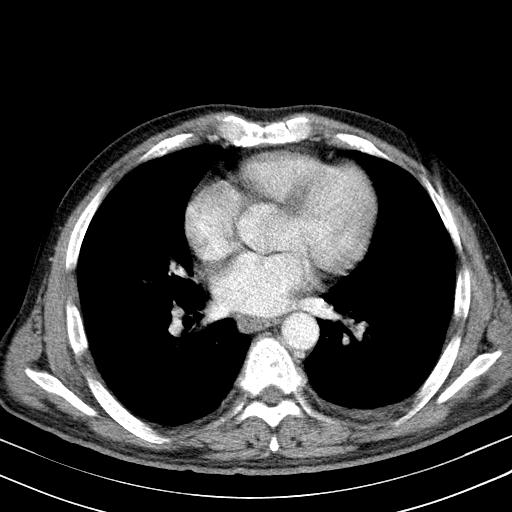

先行ct平扫,纵膈内多发软组织影,ct值约为36hu,以下为增强扫描和腹部平扫。

请会诊

经典?纵膈多发肿大淋巴结。腹膜后未见异常。

淋巴瘤?胸腺瘤?

1)考虑淋巴瘤。2)双侧少量胸腔积液。